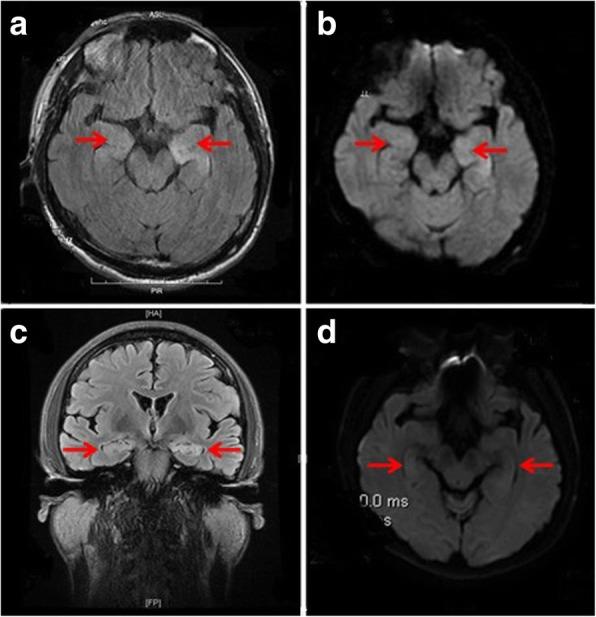

Herein, we reported a male patient presenting as rapidly progressive dementia and hyponatremia. He had antibodies targeting LGI1 both in the cerebrospinal fluid and serum, which demonstrated the diagnosis of typical anti-LGI1 AE. The scores of Mini-Mental State Examination and Montreal Cognitive Assessment were 19/30 and 15/30, respectively. Cranial magnetic resonance images indicated hyperintensities in bilateral hippocampus. The findings of brain arterial spin labeling and Fluorine-18-fluorodeoxyglucose positron emission tomography showed no abnormal perfusion/metabolism. After the combined treatment of intravenous immunoglobulin and glucocorticoid, the patient's clinical symptoms improved obviously.

在此,我们报告了一名以快速进展性痴呆和低钠血症为表现的男性患者。他的脑脊液和血清中均存在靶向LGI1的抗体,这证实了典型抗LGI1 AE的诊断。简易精神状态检查表和蒙特利尔认知评估量表的得分分别为19/30和15/30。头颅磁共振成像显示双侧海马区高信号。脑动脉自旋标记和氟代脱氧葡萄糖正电子发射断层扫描结果显示无异常灌注/代谢。经过静脉注射免疫球蛋白和糖皮质激素联合治疗后,患者的临床症状明显改善。